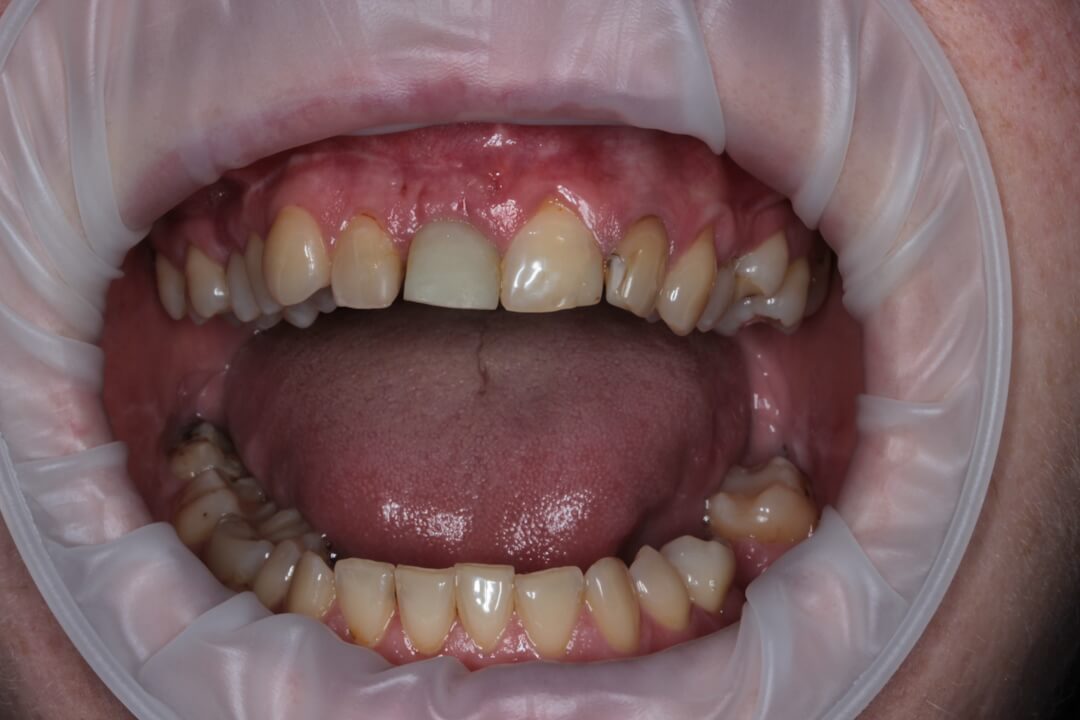

Рис. 3. Вид пациентки на 10 сутки (снятие швов).